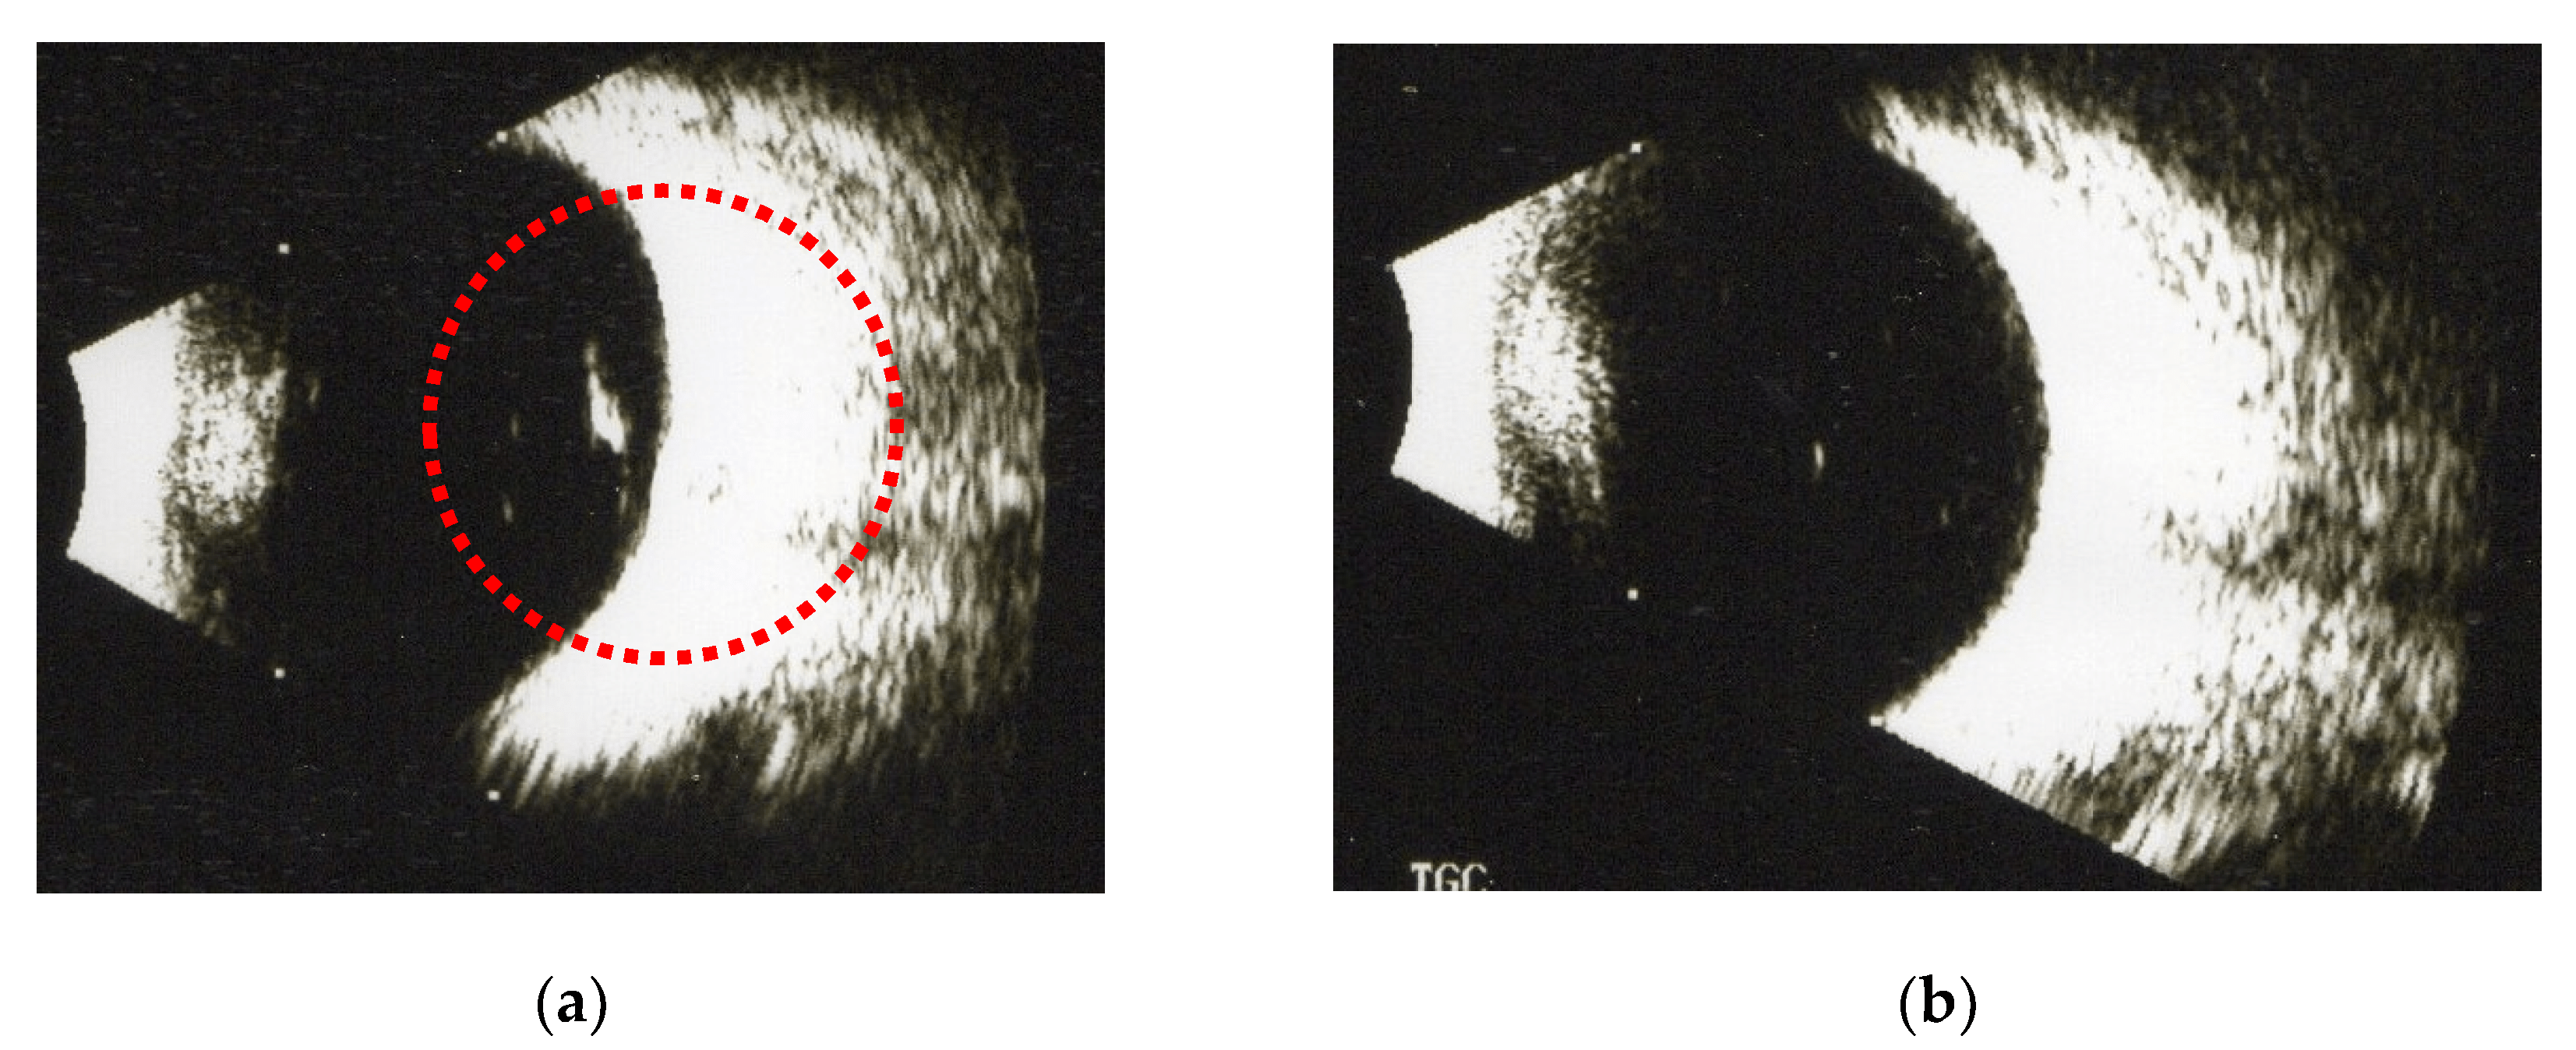

Bscan echography, left eye, demonstrated vitreous opacities but no... Download Scientific Diagram What Does Vitreous Opacities Mean Vitreous floaters may occur following a retinal tear, retinopexy, scleral buckling, or vitreous hemorrhage associated with a tear, said gaurav k. Innovations in surgical instrumentation have allowed retina surgeons to have a more robust response to treating symptomatic vitreous opacities. They may drift about when you move your eyes. Vitreous opacities (vo) are microscopic collagen fibers within the vitreous that. What Does Vitreous Opacities Mean.